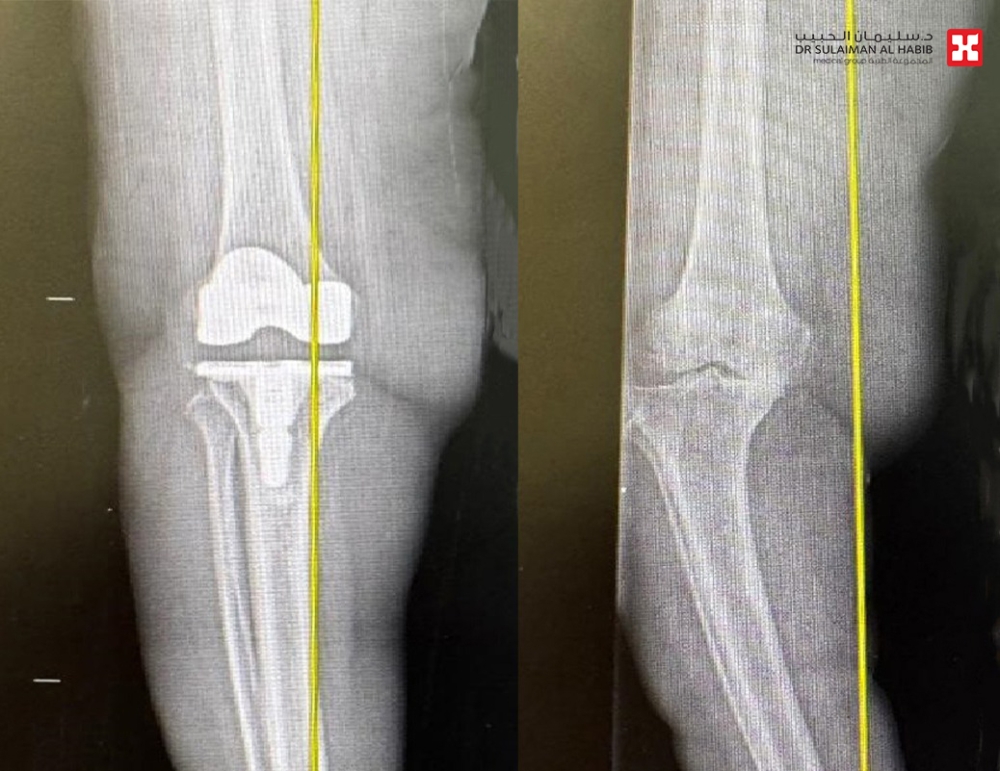

نجاح أول عملية استبدال ركبة بالروبوت الجراحي في مستشفى الدكتور سليمان الحبيب بالخبر

شهد مستشفى الدكتور سليمان الحبيب بالخبر، إجراء عملية متقدمة لاستبدال مفصل الركبة لسيدة عمرها “77” عاماً، وبحالة صحية معقدة، باستخدام تقنية الروبوت “Robotic surgery”،وتحت التخدير النصفي وأنهت العملية معاناتها مع الأعراض الحادة، ذكر ذلك د. محمد سكيك استشاري جراحة العظام والمفاصل، رئيس الفريق الطبي المعالج.

وأضاف أن المراجعة خضعت لفحوصات دقيقة، حيث كشفت صور الأشعة السينية عن وجود خشونة حادة في مفصل الركبة، وتلف بالأربطة، فقام الفريق الطبي بوضع خطة علاجية متكاملة، بعلاج هشاشة العظام، بعدها أخضعت لعملية متقدمة باستخدام تقنية الروبوت الجراحي، وتحت التخدير النصفي، وتم فيها تعديل التقوس الحاد باستخدام دعامة لتعويض تصلب وضعف الأربطة، ومن ثم استبدال مفصل الركبة بآخر صناعي عالي الجودة ومناسب للحالة. استغرقت العملية نحو “90” دقيقة، وتكللت ولله الحمد بالنجاح التام، وتمكنت المراجعة من المشي بعد ساعات قليلة من العملية، وغادرت المستشفى بعد عدة أيام، وهي بحالة صحية جيدة، ولاحقاً تخلصت من كافة الأعراض التي عانت منها طوال عامين، وعادت لممارسة حياتها الطبيعية.